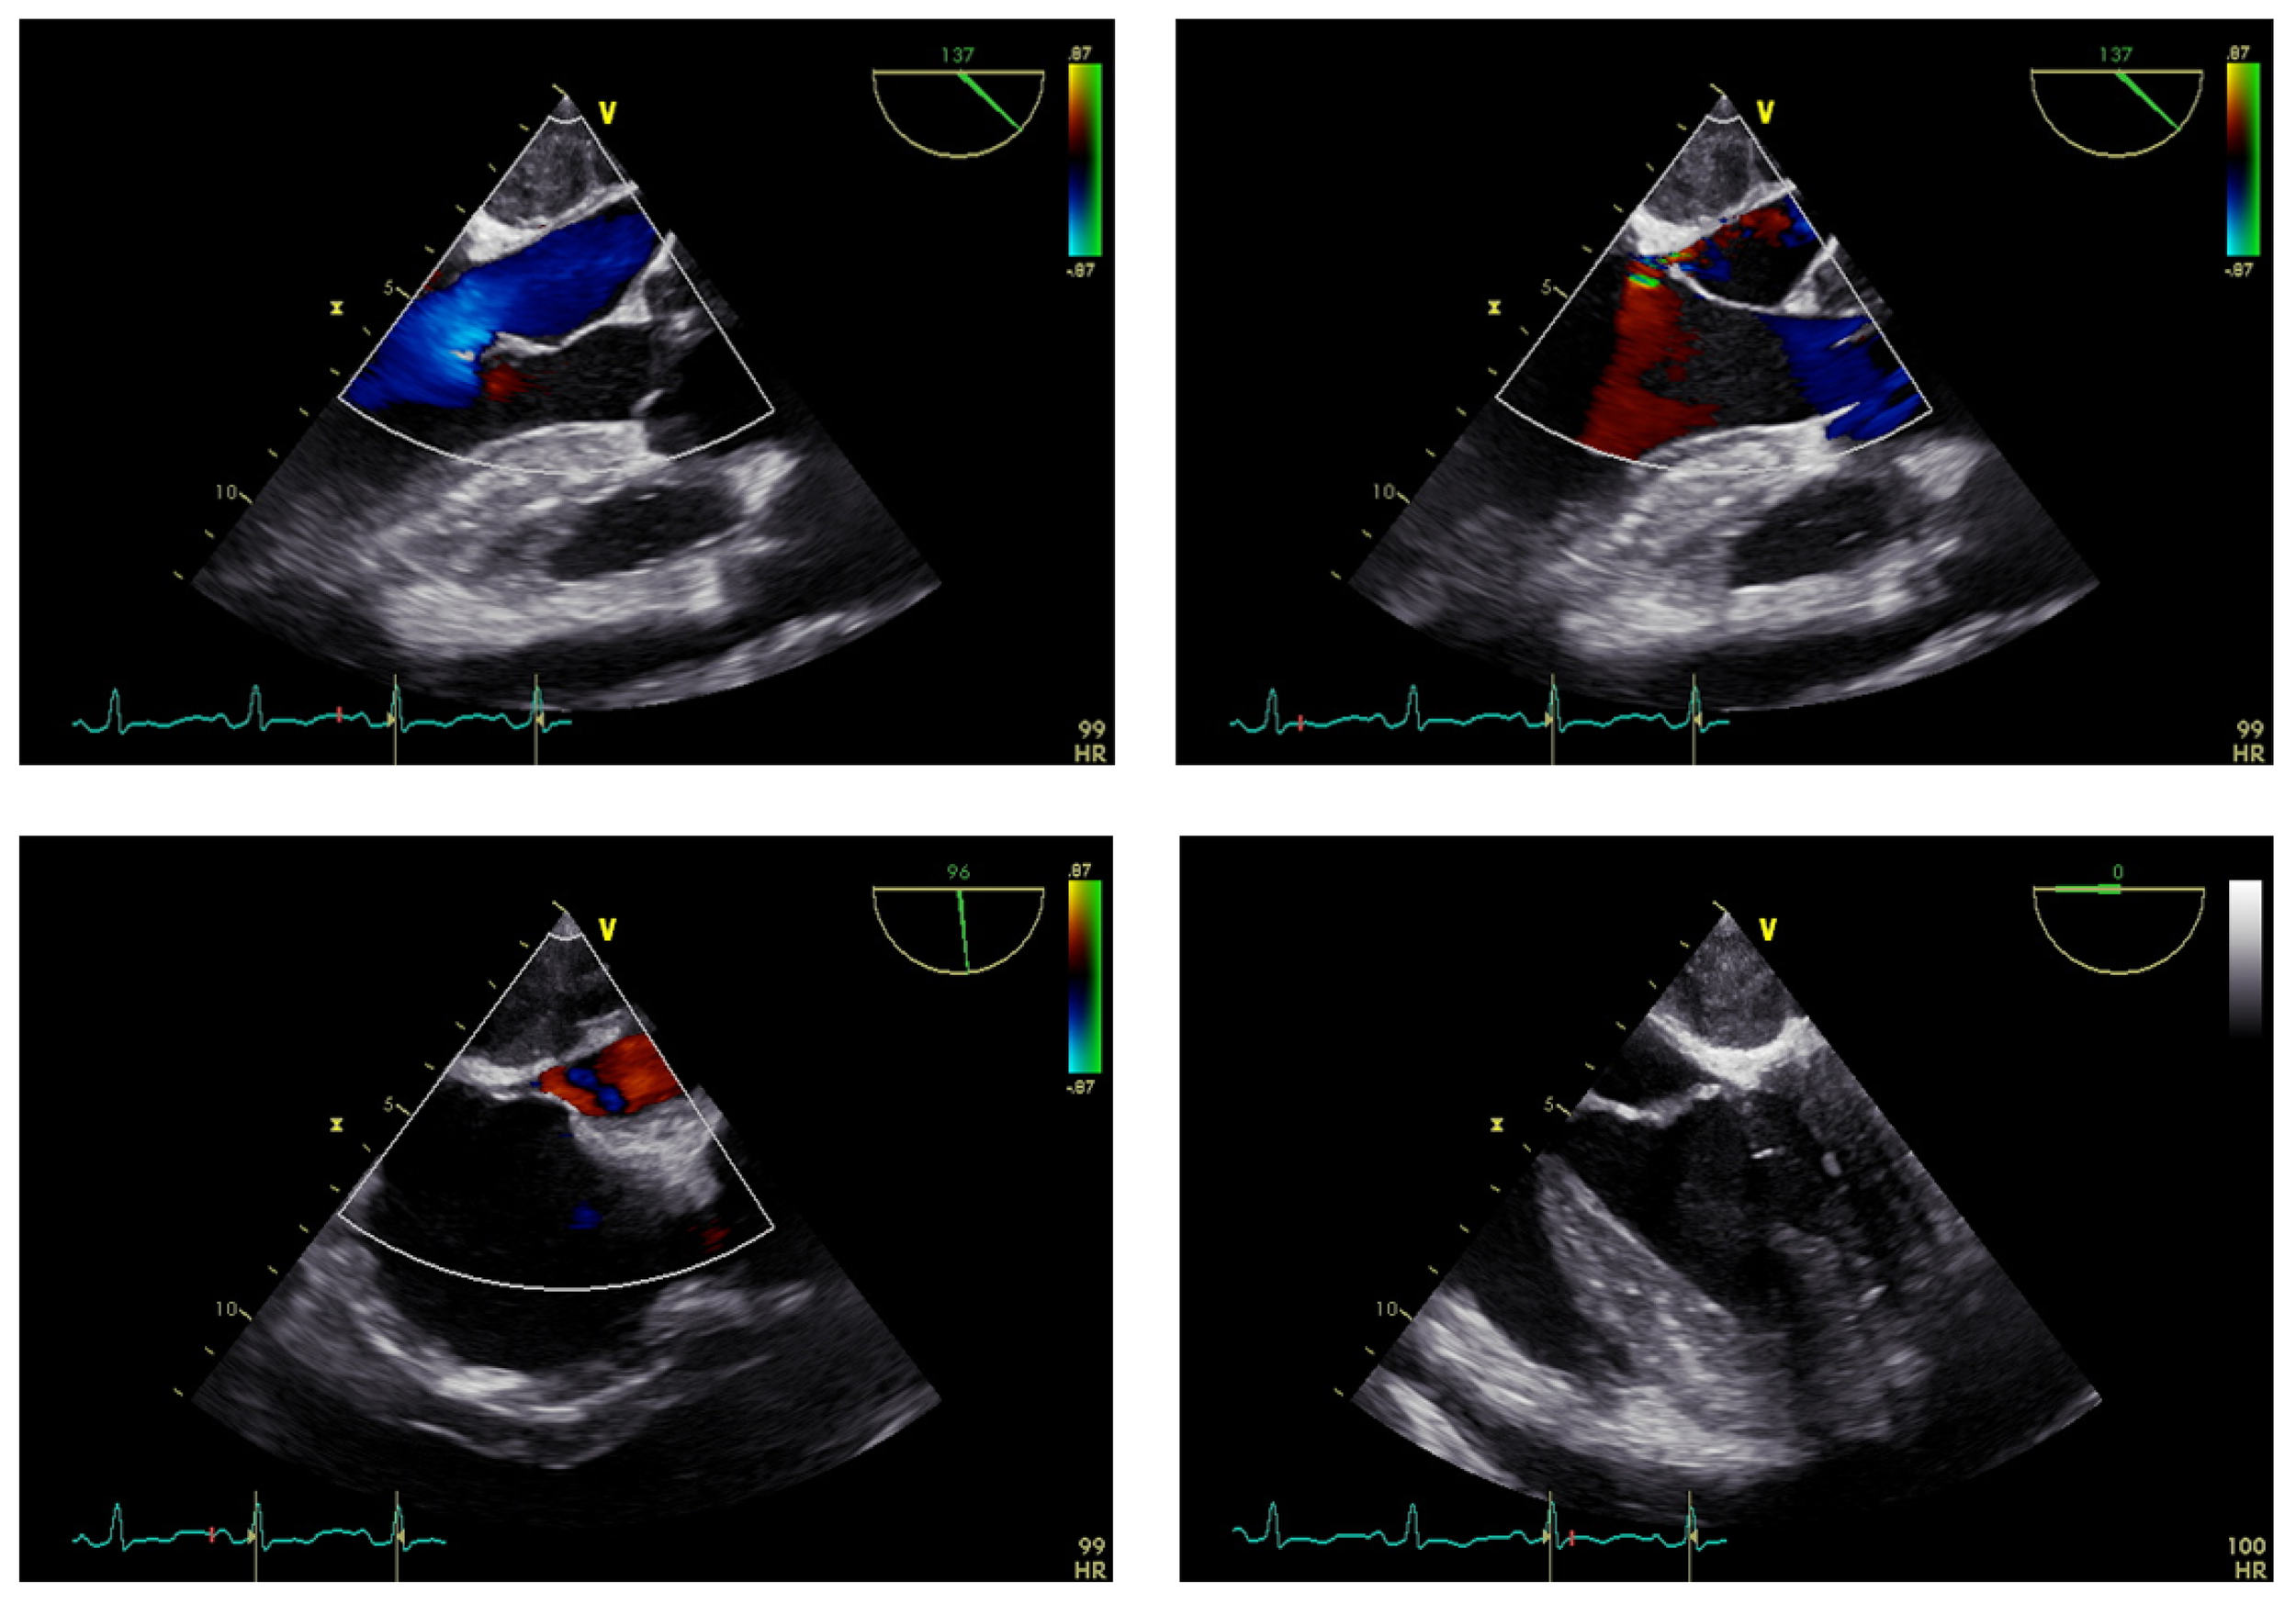

Figure 2

Preoperative TEE examination results.